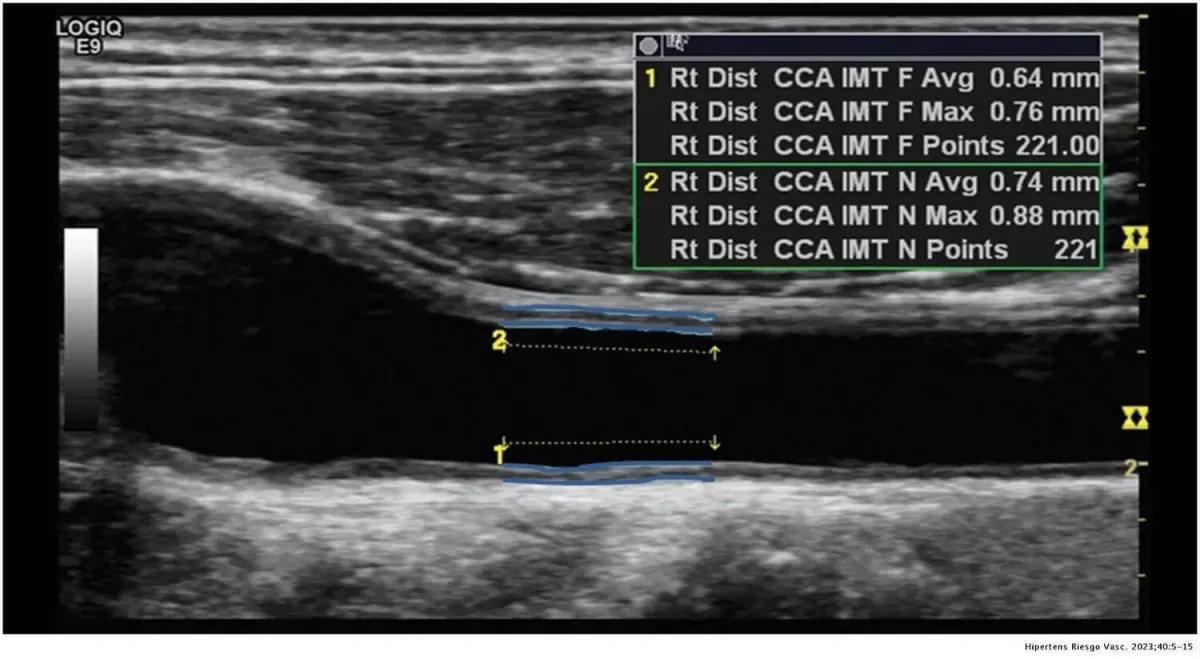

Un des moyens non-irradiant et accessible est d’évaluer l’épaisseur de l’intima-média de vos artères carotides (CIMT) sous échographie.

Un test CIMT est un examen échographique fiable et non invasif qui mesure l’épaisseur des deux couches internes de vos artères carotides. Au fur et à mesure que la plaque s’accumule, ces couches internes s’épaississent – un signe précoce d’athérosclérose, menant souvent à des maladies cardiaques et des accidents vasculaires cérébraux.

Artère carotide avec plaques très épaisses